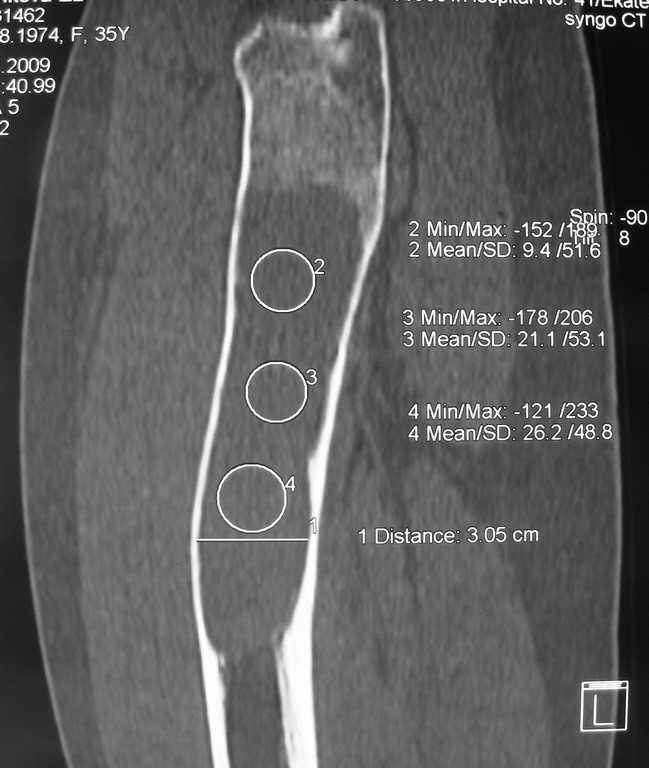

Re: Фиброзная дисплазия-продолжение

Maxim Agalakov 14 Январь 2010, 23:39

Устьянцев Ибрагимов 15 Январь 2010, 08:10

Уважаемая коллега!

Один из вариантов выбора- резекция пораженного участка, замещение дефекта по Илизарову, с последующим синостозированием или эндопротезированием.

Илья Иофин 31 Январь 2010, 03:39

Я бы сделал открытый латеральный доступ к прохимальной части бедра и провёл кюретаж. Потом бы поставил штырь типа Gamma nail. Оставшуюся от кюретажа полость следует заполнить костным цементом. Проблема при фиброзной дисплазии в том, что она через год два возвращается и "съедает" аллокость, как будто операции и не делали.

Эту операцию я бы делал только если у пациента есть симптомы боли. Если их нет, то делал бы периодический рентген бедра.